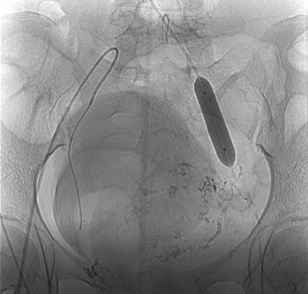

对最初针对膀胱壁成分的AVM进行部分断流,由于存在多个双侧动脉供血,完全闭塞被认为是不可行的,且非靶向栓塞的风险很高。计划是用NBCA混合碘油对滋养动脉进行超选择性分别栓塞,其浓度取决于选择性血管造影术的可行以及血流速度。防止NBCA向肺循环迁移是非常必要的。髂内静脉逆行球囊辅阻断,以减少血流。

球囊经右颈内静脉入路,膨胀于左髂内静脉